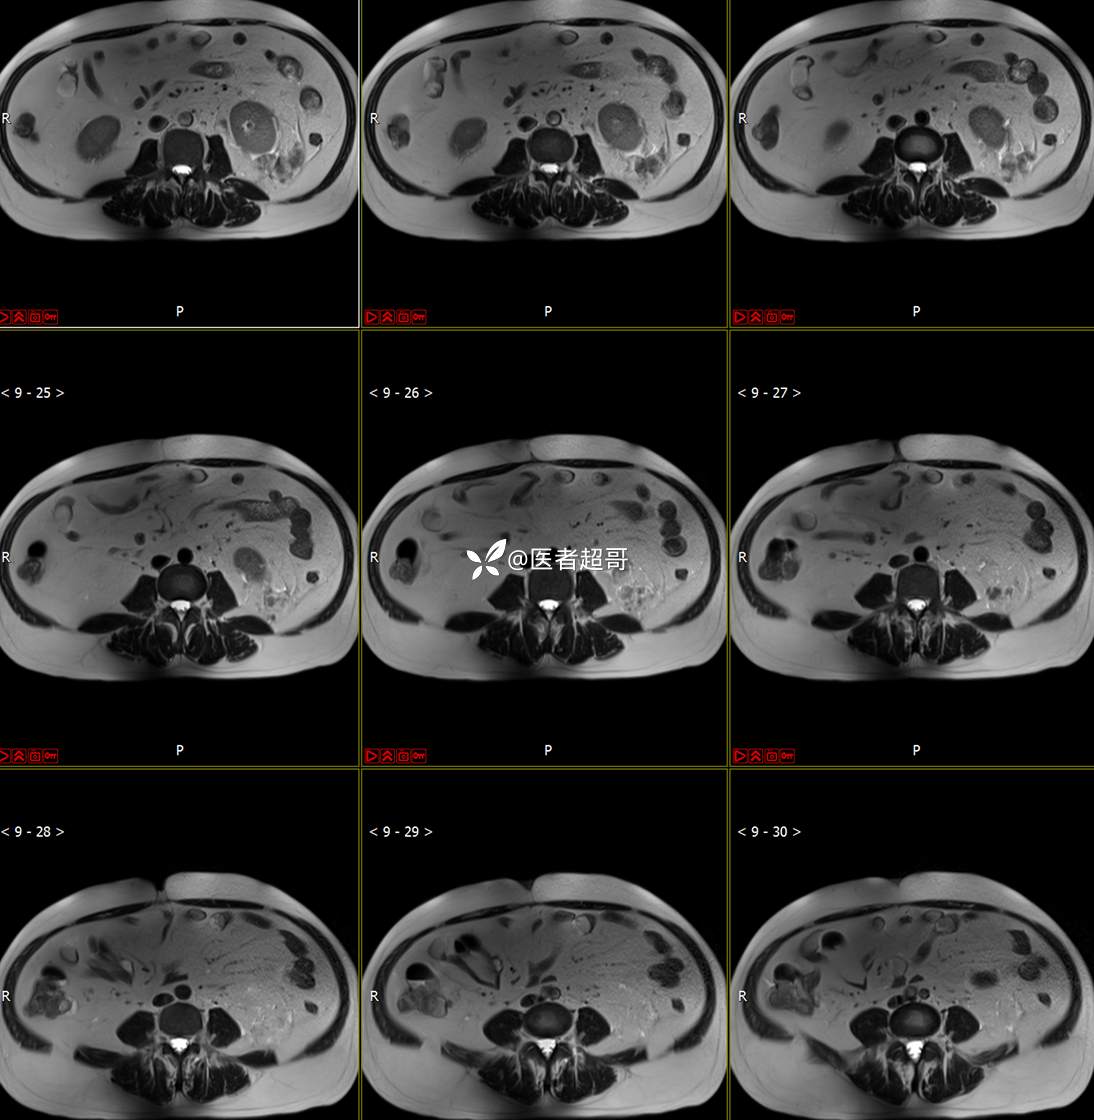

主 诉:查体发现左肾肿物9天。

现病史:患者9天前于附属医院行常规腹部CT检查时,发现左肾占位性病变并肾周脂间隙软组织增多,自述无明显腰腹部不适,无尿频、尿急、尿痛及肉眼血尿,未予特殊治疗,患者近期无头晕头迷,胸闷气急,腹胀腹泻及其他部位明显不适,遂至我院就诊,门诊以“肾肿物”收入院,患者自发病以来,精神可,睡眠饮食可,大便正常,体重无明显减轻。